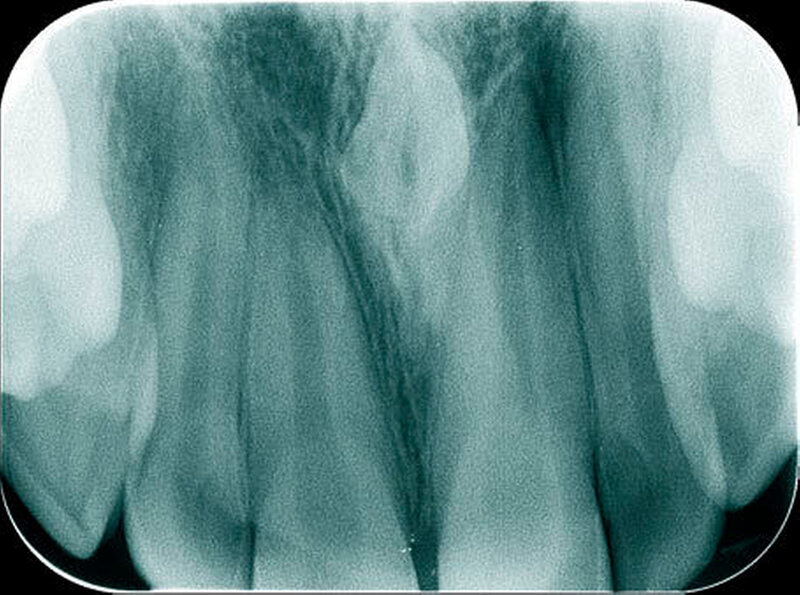

Überzählige Zähne sind die häufigste Ursache für einen unterbliebenen oder verzögerten Durchbruch der oberen Schneidezähne (Abbildungen 13, 14, 15) [Betts Camilleri, 1999]. Besonders beim höckerförmigen Typ kommt es häufig zu Störungen der Eruption der oberen Schneidezähne [Mason et al., 2000]. Diese Komplikation macht sich klinisch initial dadurch bemerkbar, dass die oberen seitlichen Schneidezähne durchbrechen und die Eruption von einem oder beiden zentralen Schneidezähnen ausbleibt [Rajab Hamdan, 2002]. Auch in anderen Lokalisationen der Kiefer können überzählige Zähne zu Durchbruchsstörungen benachbarter Zähne führen [Garvey et al., 1999; Rajab Hamdan, 2002; Mossaz et al., 2014]. Insgesamt liegt die Prävalenz für den Ausfall des Durchbruchs bleibender Zähne bedingt durch überzählige Zähne zwischen 10,2 Prozent und 61 Prozent [Tay et al., 1984; Koch et al., 1986; Tyrologou et al., 2005; Fernández Montenegro et al., 2006; Liu et al., 2007; Gündüz et al., 2008; Hyun et al., 2009; Mínguez-Martinez et al., 2012; Mossaz et al., 2014].

Überzählige Zähne können bei Nachbarzähnen von einer leichten Rotation bis hin zu einer körperlichen Verschiebung alle Formen der Lageveränderungen bewirken. Studien zeigen auf, dass etwa bei einem Drittel der überzähligen Zähne eine Verschiebung des benachbarten Zahns resultiert [Koch et al., 1986; von Arx, 1990; Tyrologou et al., 2005; Liu et al., 2007; Gündüz et al., 2008; Mossaz et al., 2014]. Tay und Mitarbeiter (1984) berichteten gar über eine noch höhere Prävalenz von 55 Prozent. Hyun und Mitarbeiter (2009) betonen, dass überzählige Zähne im Oberkieferfrontzahnbereich nicht selten auch zu einer Diastemabildung führen, was für die Therapieplanung von Bedeutung ist (Abbildungen 16 uns 17).